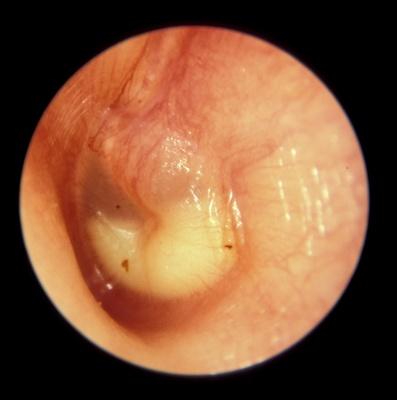

Los síntomas pueden estar ausentes o pasar desapercibidos, sobre todo en la primera infancia y en los estadios crónicos de la enfermedad. El tímpano puede estar oculto por el cerumen, cuya extracción puede ser muy complicada y laboriosa.

Las anomalías del tímpano pueden ser muy sutiles y difíciles de apreciar. Debido a estas dificultades, se realizan frecuentemente tanto sobrediagnósticos como infradiagnósticos.

Los síntomas y los signos de la OMA son muy variables, sobre todo en los lactantes y en los niños pequeños.

Pueden existir signos de otalgia, que suele manifestarse por irritabilidad, cambios en los hábitos de sueño o de alimentación y, en ocasiones, porque el niño se lleva las manos o se da tirones de las orejas. Sin embargo, el tirarse de la oreja tiene poca sensibilidad y especificidad.

También puede haber fiebre y, en pocas ocasiones, una rotura de la membrana timpánica con otorrea purulenta. También existen síntomas sistémicos y de afectación de las vías respiratorias altas, aunque a veces el niño está asintomático y la OMA se descubre en un reconocimiento médico rutinario.

La OMD no se suele acompañar de una sintomatología muy llamativa, pero suele asociarse a una hipoacusia, que puede manifestarse como alteraciones de los patrones del habla, pero a menudo no se detecta si es unilateral o leve, sobre todo en los niños más pequeños. La OMD también puede asociarse a alteraciones del equilibrio o a desequilibrio, y los niños más mayores pueden referir molestias leves o de una sensación de plenitud en el oído

Perforación de la membrana timpánica

La rotura de la membrana timpánica puede producirse tanto con episodios de OMA como de

OMD. Aunque la lesión de la membrana debida a estos episodios suele cicatrizar de forma espontánea, en un pequeño número de casos pueden producirse perforaciones crónicas que requerirán un tratamiento quirúrgico posterior.